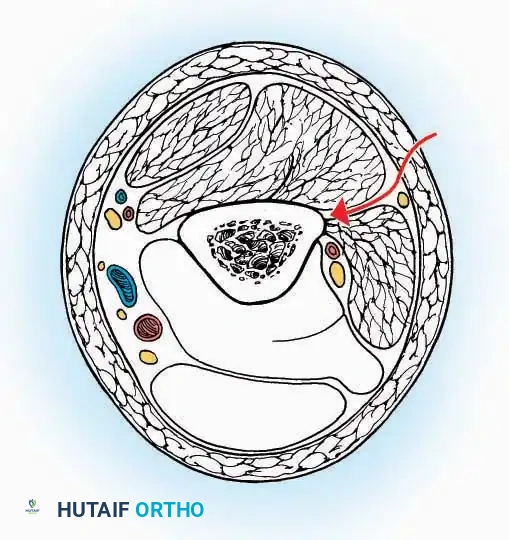

* Internervous Plane: The deep dissection exploits the plane between the Extensor Hallucis Longus (EHL) tendon (innervated by the deep peroneal nerve) and the Extensor Digitorum Longus (EDL) tendons (also innervated by the deep peroneal nerve).

* Neurovascular Bundle: Incise the extensor retinaculum. Carefully identify the anterior tibial artery and the deep peroneal nerve, which typically lie between the EHL and EDL, or directly deep to the EHL. Retract the neurovascular bundle laterally with the EDL, or medially with the EHL, depending on the specific anatomical variant encountered (lateral retraction is most common).